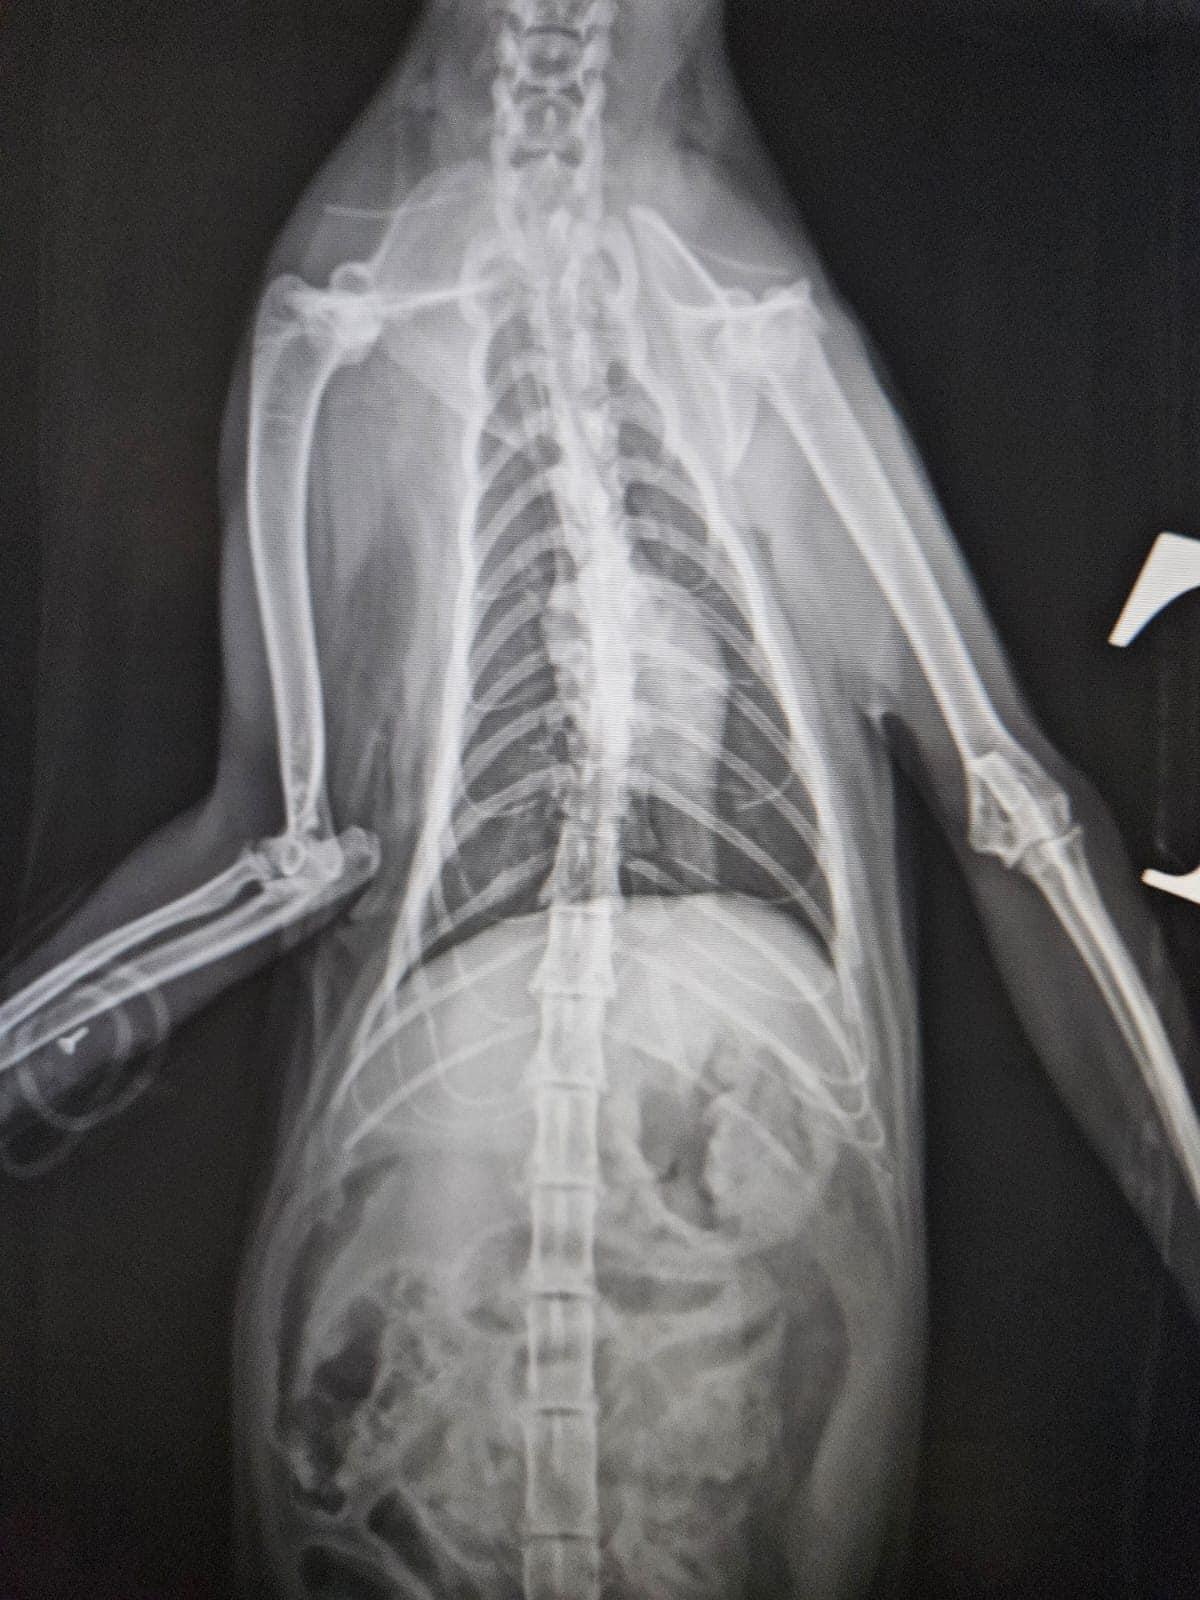

社交平台Facebook專頁「毛守救援」凌晨表示,昨晚錦田公路石崗菜站,有一隻雌性唐貓懷疑被白色私家車撞到,涉事司機不顧而去,捱撞唐貓重創倒臥路中,口鼻吐血,大腿位置有傷口,情況嚴重,有熱心司機見狀通知「毛守救援」,將受傷貓隻事後被送往動物診所接受搶救。

毛守救援上載多張照片和多條影片,可見唐貓倒在馬路,附近遺下血跡,一把女聲表示「撐住呀貓貓」。毛守救援指出,受傷唐貓已經接受絕育和剪耳,頸部戴上蝨帶,估計有主人,呼籲如有街坊認識受傷貓咪主人, 請致電6999 4221。